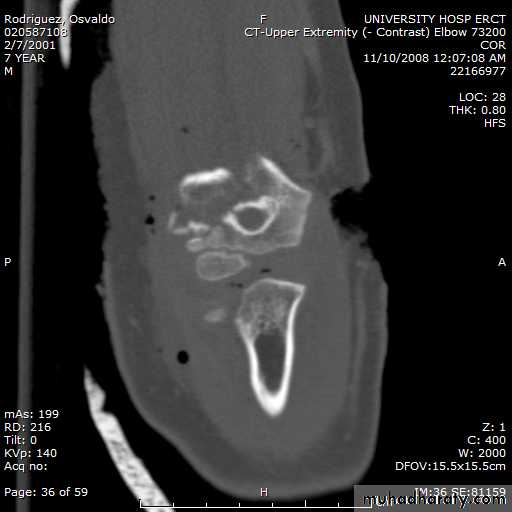

8 y.o. rolled over on an ATV

with mild closed head injuryClinical appearance

Only N-V deficit:

Anterior interosseous n. function weak

Radial A.

FCR Musc.Imaging Studies

How are we going to stabilize this boy’s fracture?

This is probably one of the few indication to use

Antegrade Flexible I M NailsOur Patient P.O.